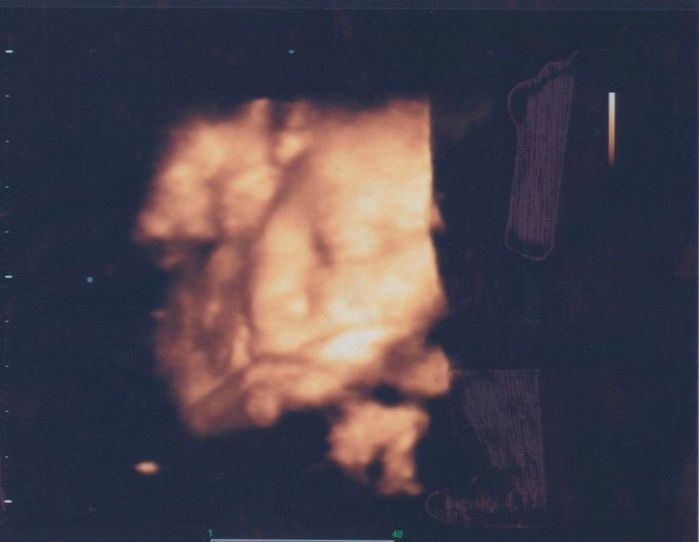

初めての4Dエコーに成功 - 妊娠27週目のエコー写真

推定体重1000g 初めての4Dエコーに成功

初めて4Dエコーに成功! 手が顔の前にあるけど、ちゃんとお顔を見せてくれました。目、鼻、口がこんなにもはっきりと映るのかと驚きました。「鼻はパパ似!? 口はママ似!? 」と話が盛り上がりました。とにかくかわいくて愛おしくて仕方がありません。この日の検診で血糖値が引っかかってしまい、再検査となりました。ここ最近はとにかく果物が食べたくて仕方なく、「その影響もあったのかな? 」と反省しました。